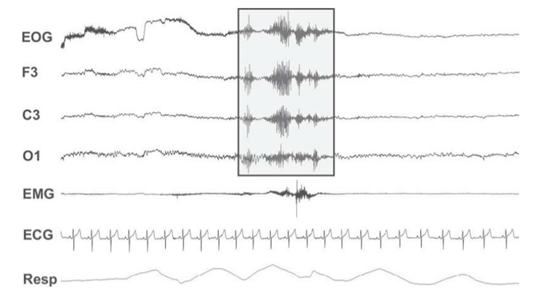

注:浅灰色框勾勒出典型的自发性皮层唤醒,以 EEG 频率的突然变化为标志

图1 20 秒多导睡眠图 (PSG) 睡眠追踪的代表性图像,包括眼电图 、脑电图 (F3、C3 和 O1 导联)、咀嚼肌表面肌电图、心电图和呼吸